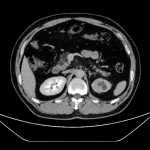

左側(cè)輸尿管惡性腫瘤的臨床診療經(jīng)驗(yàn)分享 現(xiàn)病史【一般資料】 男性,51,職員 【主訴】 間斷血尿4月余 【現(xiàn)病史】 患者4月余前無明顯誘因出現(xiàn)間斷血尿,無腰腹部疼痛、發(fā)熱、腹脹、咳嗽、咳痰等不適,未進(jìn)行針對(duì)性診治,上述癥狀反復(fù)出現(xiàn)。為明確病因、規(guī)范治療,遂來我院就診,門診結(jié)合癥狀及初步檢查,以相關(guān)病癥收住入院?;颊咦园l(fā)病以來,精神狀態(tài)尚可,飲食